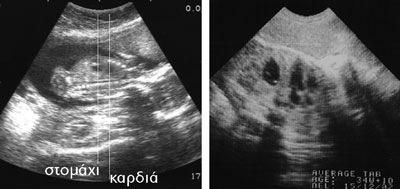

Εικόνα 1. Φυσιολογική τοπογραφική αλληλοσυσχέτιση καρδιάς-στομάχου σε έμβρυο ηλικίας 17 εβδομάδων (αριστερά) και 34 εβδομάδων (δεξιά) σε επιμήκη τομή. Είναι εμφανής η διαφορά επιπέδου των δύο οργάνων σε αντίθεση με αυτό που συμβαίνει σε περίπτωση διαφραγματοκήλης όπου συμπίπτουν και προβάλονται στο ίδιο επίπεδο (Εικ. 2).